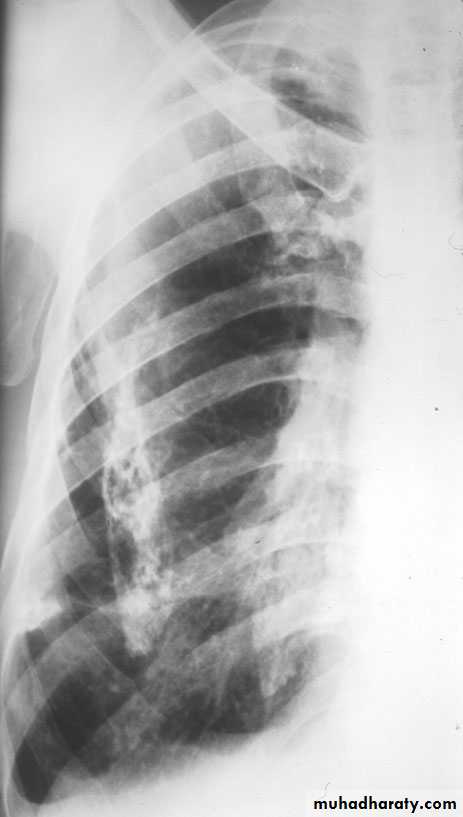

2- lateral.

Lateral view position